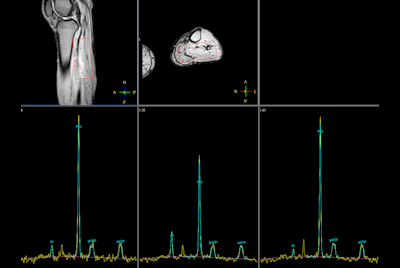

Multi Nuclei - Dynamic calf muscle imaging (31P)